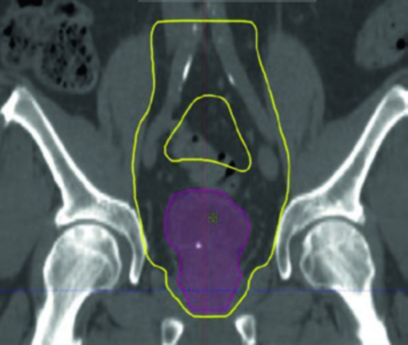

Los protocolos RTOG 0712 y 0926 definen un abordaje secuencial en dos fases. El campo pélvico pequeño (CTV4140) abarca la vejiga completa, próstata y uretra prostática (varones), uretra proximal (mujeres) y linfáticos regionales. Le sigue un cone down al campo de vejiga total (CTV6120) que incluye la vejiga entera y cualquier volumen tumoral macroscópico (GTV).

El campo pélvico pequeño se planifica como un arreglo four-field box. El campo de vejiga total puede utilizar four-field box o laterales opuestos paralelos, con colimador multiláminas para optimizar la conformación. Se recomienda el contorneo de ganglios pélvicos para asegurar que los campos estándar engloben los linfáticos en riesgo, ajustando bordes según sea necesario.